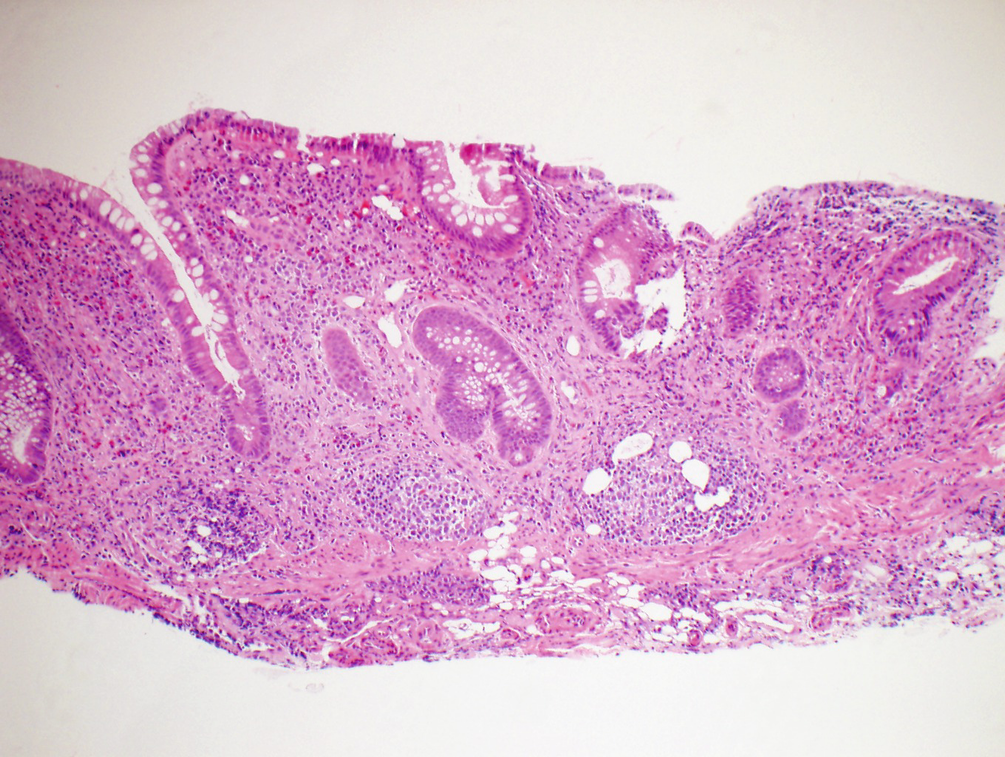

This type of inflammatory bowel disease ibd causes sores in the intestines. There is a change in the texture of your poop. Excess mucus in the stool might be a sign of a gastrointestinal gi problem.

Blood tons of mucus or bloody mucus in your stool is always a cause for concern especially if its accompanied by abdominal pain or other symptoms. Stool normally contains a small amount of mucus a jellylike substance that your intestines make to keep the lining of your colon moist and lubricated. They can bleed and make pus and mucus.

According to the world journal of gastroenterology if an inflammatory process breaks down this mucosal layer. It is a regular occurrence. Irritable bowel syndrome ibs is a common gut disorder.